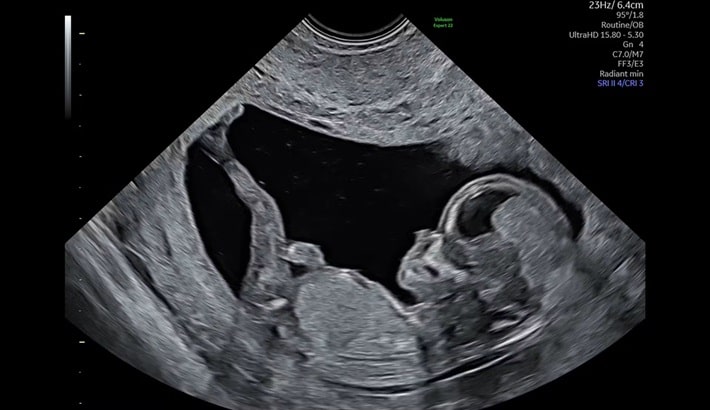

سونوگرافی آنومالی یکی از اصلیترین مراحل بررسی سلامت جنین در دوران بارداری است. این سونوگرافی معمولاً بین هفتههای ۱۸ تا ۲۲ بارداری انجام میشود و هدف آن بررسی جزئیترین قسمتهای بدن جنین است. پزشک با کمک تصاویر دقیق، رشد اندامها و وجود احتمالی ناهنجاریهای مادرزادی را کنترل میکند.

بازه زمانی مشخصی برای انجام این سونوگرافی وجود دارد. اگر زودتر یا دیرتر از هفتههای تعیینشده انجام شود، ممکن است دقت تصاویر کمتر باشد. پزشکان معمولاً هفته ۲۰ بارداری را بهترین زمان معرفی میکنند؛ چون در این مرحله جنین بهاندازهای رشد کرده که اندامهایش بهطور واضح قابل بررسی باشند.

دستها، پاها و انگشتان جنین در سونوگرافی آنومالی بهوضوح دیده میشوند. این بخش برای والدین بسیار هیجانانگیز است، زیرا اولین بار است که حرکات کوچک جنین را میبینند.